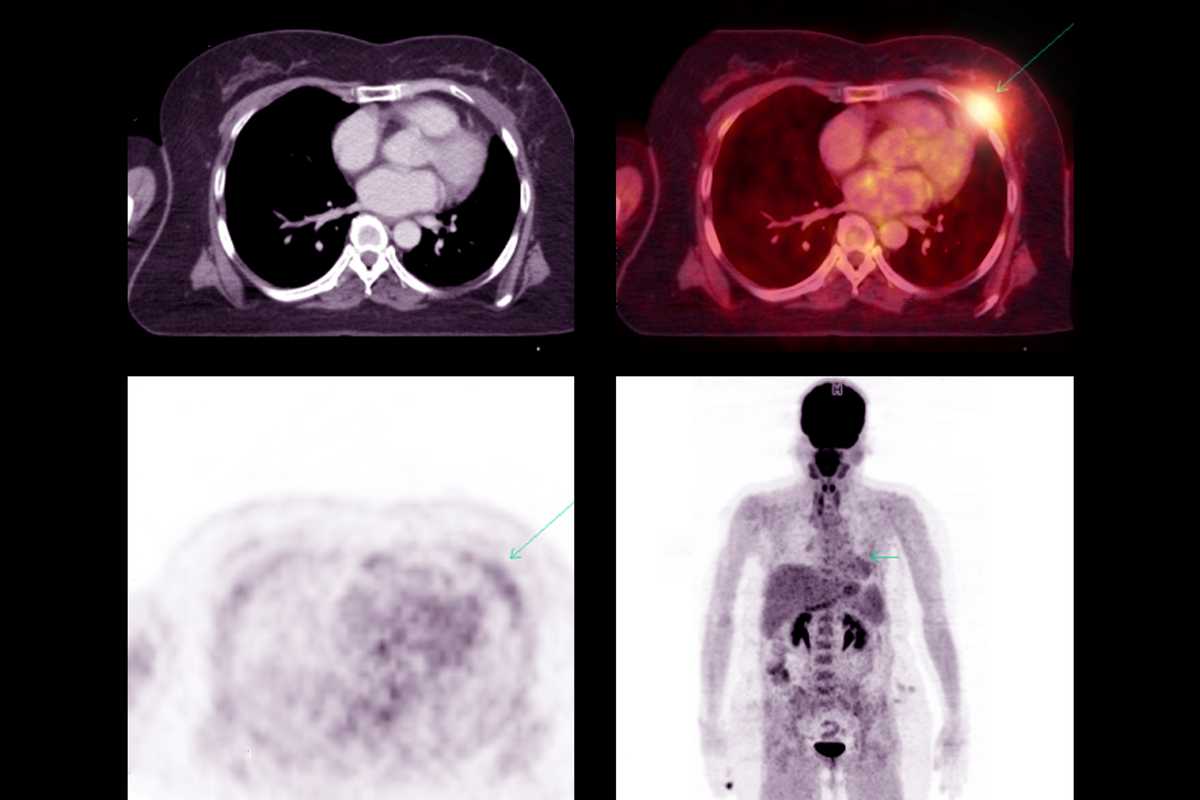

In a study published March 1 in the Journal of Nuclear Medicine, Abhinav Jha, assistant professor of biomedical engineering at the McKelvey School of Engineering and of radiology at the Mallinckrodt Institute of Radiology at the School of Medicine, both at Washington University in St. Louis, examined positron emission tomography (PET) segmentation algorithms.

“Image segmentation is a burdensome task,” Jha explained. “It requires drawing a 3D boundary around an object of interest – such as a tumor – in an image with a lot of variability in quality, resolution and other factors that make accurate segmentation difficult. AI algorithms have the potential to do this task accurately, precisely, quickly and cheaply, reducing the burden on doctors. These algorithms are already being used in clinical settings now, but every algorithm can give different boundaries, so how do we know which is most accurate?”

Jha and his collaborators, Joyce Mhlanga, MD, associate professor of radiology, and Barry Siegel, MD, professor of radiology and medicine, both at WashU’s School of Medicine, compared traditional metrics used to evaluate segmentation algorithms, which generally considered the volume overlap and shape of the segmentation, with metrics focused on quantifying how large and metabolically active a tumor is. They asked, does the evaluation of segmentation algorithms using task-agnostic metrics correlate with performance that quantify performance on clinically relevant tasks?